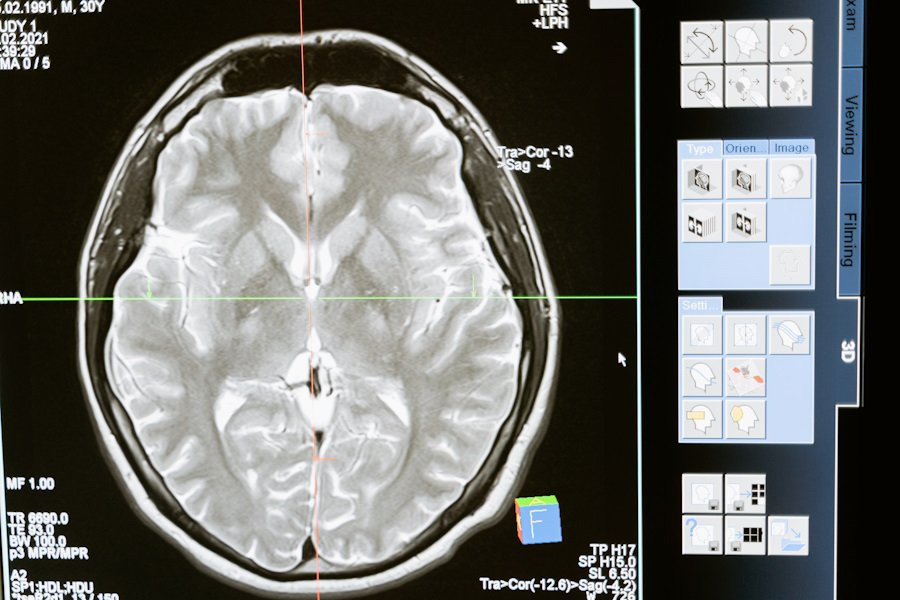

Исследователи из Institute for Basic Science (IBS) (Республика Корея) провели успешные испытания новой методики Magnetogenetic Interface for NeuroDynamics (Nano-MIND), которая позволяет воздействовать на мозг человека без использования имплантатов. Эта технология объединяет магнитные поля и намагниченные наночастицы, что открывает новые возможности для нейромодуляции, сообщает портал Nature.